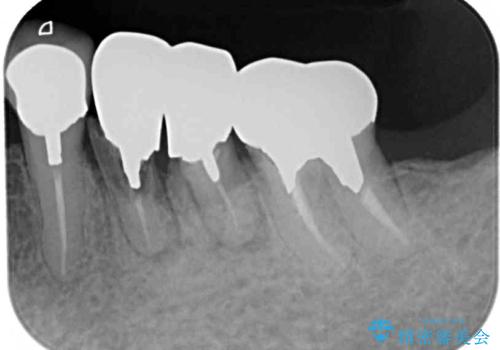

抜かずに保存した奥歯が痛くて臭う セラミックブリッジによる欠損補綴治療

- 以前抜歯を回避するために奥歯を分割して保存してもらったものの、痛みと異臭が気になるとのことで来院された患者様です。

診査したところ、保存は不可能と診断しました。

前後の歯も大きな銀歯が装着されていたので、抜歯後に治癒を待って、フルジルコニアブリッジにて補綴することとしました。

前後の歯はいずれも神経が取り除かれている歯であったので、ブリッジ治療では負担が大きくなることが懸念されました。咬合力はさほど強くない咬み合わせであったので、インプラントではなく、ブリッジ治療を選択されました。